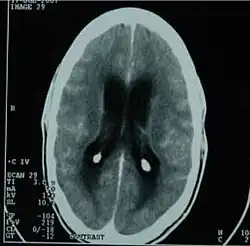

CT scan showing tuberculous meningitis